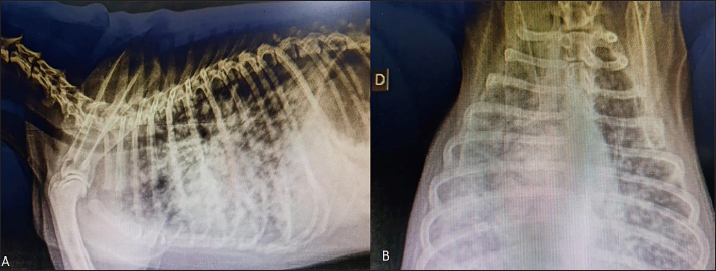

One hundred and thirty days after surgery, the patient started experiencing respiratory distress, and two-view radiographic images suggested distant metastasis (Fig. 4). Unfortunately, the patient died in the clinic and necropsy was not authorized by the owner.

Fig. 4. Radiographic two-view projections of a canine diagnosed with ureteral well-differentiated leiomyosarcoma. (A) Latero-lateral projection showing diffuse multiple nodules in the lungs. (B) Ventrodorsal projection with diffuse multiple nodules suggestive of pulmonary metastasis.

In our case, surgical resection was the treatment of choice and adjuvant chemotherapy was not prescribed at the owner’s request. During the follow-up, distant metastases occurred, leading to respiratory distress and death. The survival time was 4 months.